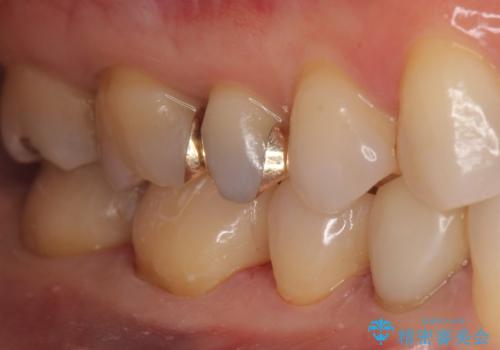

下の歯の銀歯が目立つ

- 口を開けた時、銀の詰め物が目立つとのことで来院。

拡大鏡下で詰め物を外し、う蝕がない事を確認して、セラミック(e-maxインレー)で治療を行いました。

- e-maxインレー 7.7万円×2本費用は治療当時の料金となります

銀の詰め物は歯質との間の隙間ができやすく

虫歯の再発リスクが高いです。

セラミックの詰め物(e-maxインレー)は歯質との隙間ができにくく

虫歯の再発リスクが低くなります。

口を開けた時、銀歯が目立たなくなり、大変満足して頂けました。